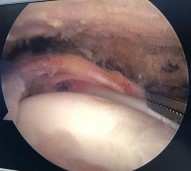

Hình phụ lục 2B:Hình ảnh rách rất rộng gân trên gai, dưới gai, khoảng gian chóp xoay; hình ảnh khâu khép rìa gân rách.

(Nguồn: BN nghiên cứu)

Đây là ca lâm sàng điển hình rách hình chữ U theo phân loại của Burkhart, nếu chỉ dựa trên phim CHT trước mổ thì rất khó xác định chính xác hình thái rách và dựa trên phim CHT trước mổ thì tiên lượng khâu được gân rất khó khăn, tuy nhiên sau khi nhận định hình dạng của gân rách chúng tôi tiến hành khâu khép rìa làm thu nhỏ gân rách tạo vi tổn thương tại diện bám, và khâu phục hồi vị trí bám của gân vào củ lớn xương cánh tay bằng 02 neo đôi. Trường hợp rách rất rộng này nếu không tiến hành khâu khép rìa gân rách mà tiến hành khâu kéo trực tiếp đầu gân rách về vùng diện bám sẽ khiến gân căng khó kéo và dễ tạo tai chó hai bên mép của vết rách. Với những trường hợp này khó xác định mốc để đặt neo nếu không dựa vào các mốc và các chỉ số giải phẫu về bờ ngoài gân.